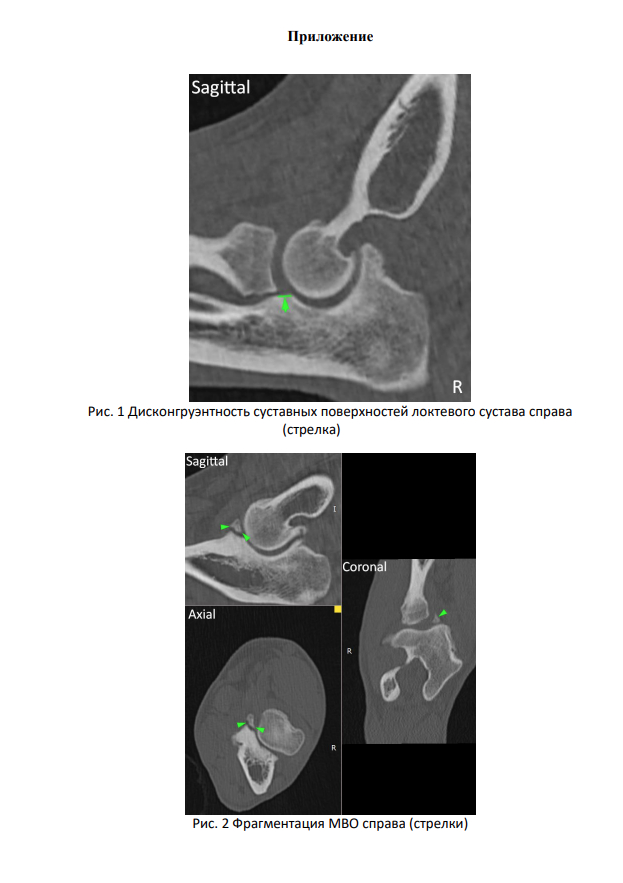

Операция на локтевом суставе у щенка немецкой овчарки

Диспозиция такая, щенок немецкой овчарки 8 мес. начал прихрамывать на переднюю правую лапу. Обратились в клинику, поставили предварительный диагноз "дисплазия правого локтевого сустава, фрагментация медиального венечного отростка", отправили на КТ, которое подтвердило диагноз "фрагментация медиального венечного отростка справа. Дисконгруэнтность суставных поверхностей (эффект ступеньки) правого локтевого сустава. Дисплазия правого локтевого сустава.".

Для "шарящих" прикрепляю картинки из клиник и видос как хромает.